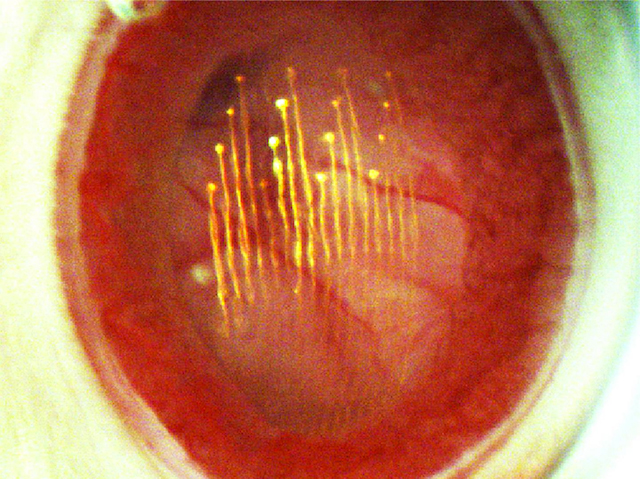

Mirant als Ulls+

Mirant als Ulls+26 de juliol de 2018